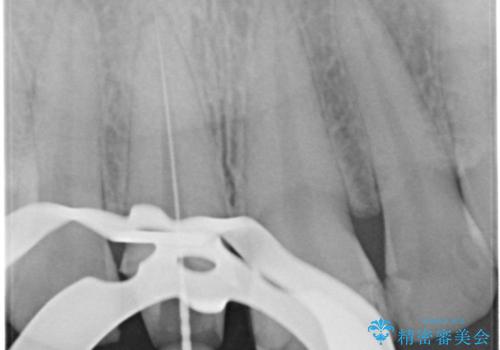

- 前歯一本だけ色が暗いことが気になりご相談にいらした患者様です。周辺の歯と色味をぴったり合わせることで自然な仕上がりになりました。

- 16万円(精密根管治療は別途)費用は治療当時の料金となります

根管治療をした歯は神経のある歯と比較して強度が下がり、長期的に破折のリスクが高まると言われています。破折のリスクを軽減させるため、根管治療を行った歯に対しては歯冠をすべて覆うクラウンという被せ物にて補綴処置を行います。

適合不良の補綴物は二次的な虫歯発生のリスクが高まります。

自費診療で用いられる材料は保険適応の材料に比べて、より精密で適合の良い被せ物作ることができるため、長期的な虫歯のリスクを大幅に減らすことが可能です。